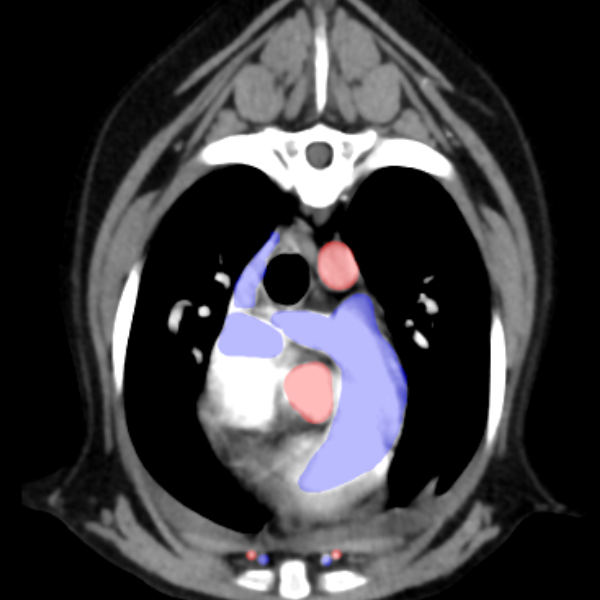

A telerradiologia é oferecida para exames radiográficos e de Tomografia Computadorizada Veterinária de todas as espécies. Empresas parceiras nos enviam os exames de imagem através do sistema PACS no formato DICOM (imagens médicas) para total segurança da preservação dos dados dos clientes. Nossa equipe avalia as imagens e elabora o laudo dentro de prazos pré-estabelecidos tanto de exames comuns como emergenciais. Para saber sobre valores e contratação entre em contato com nossa equipe.